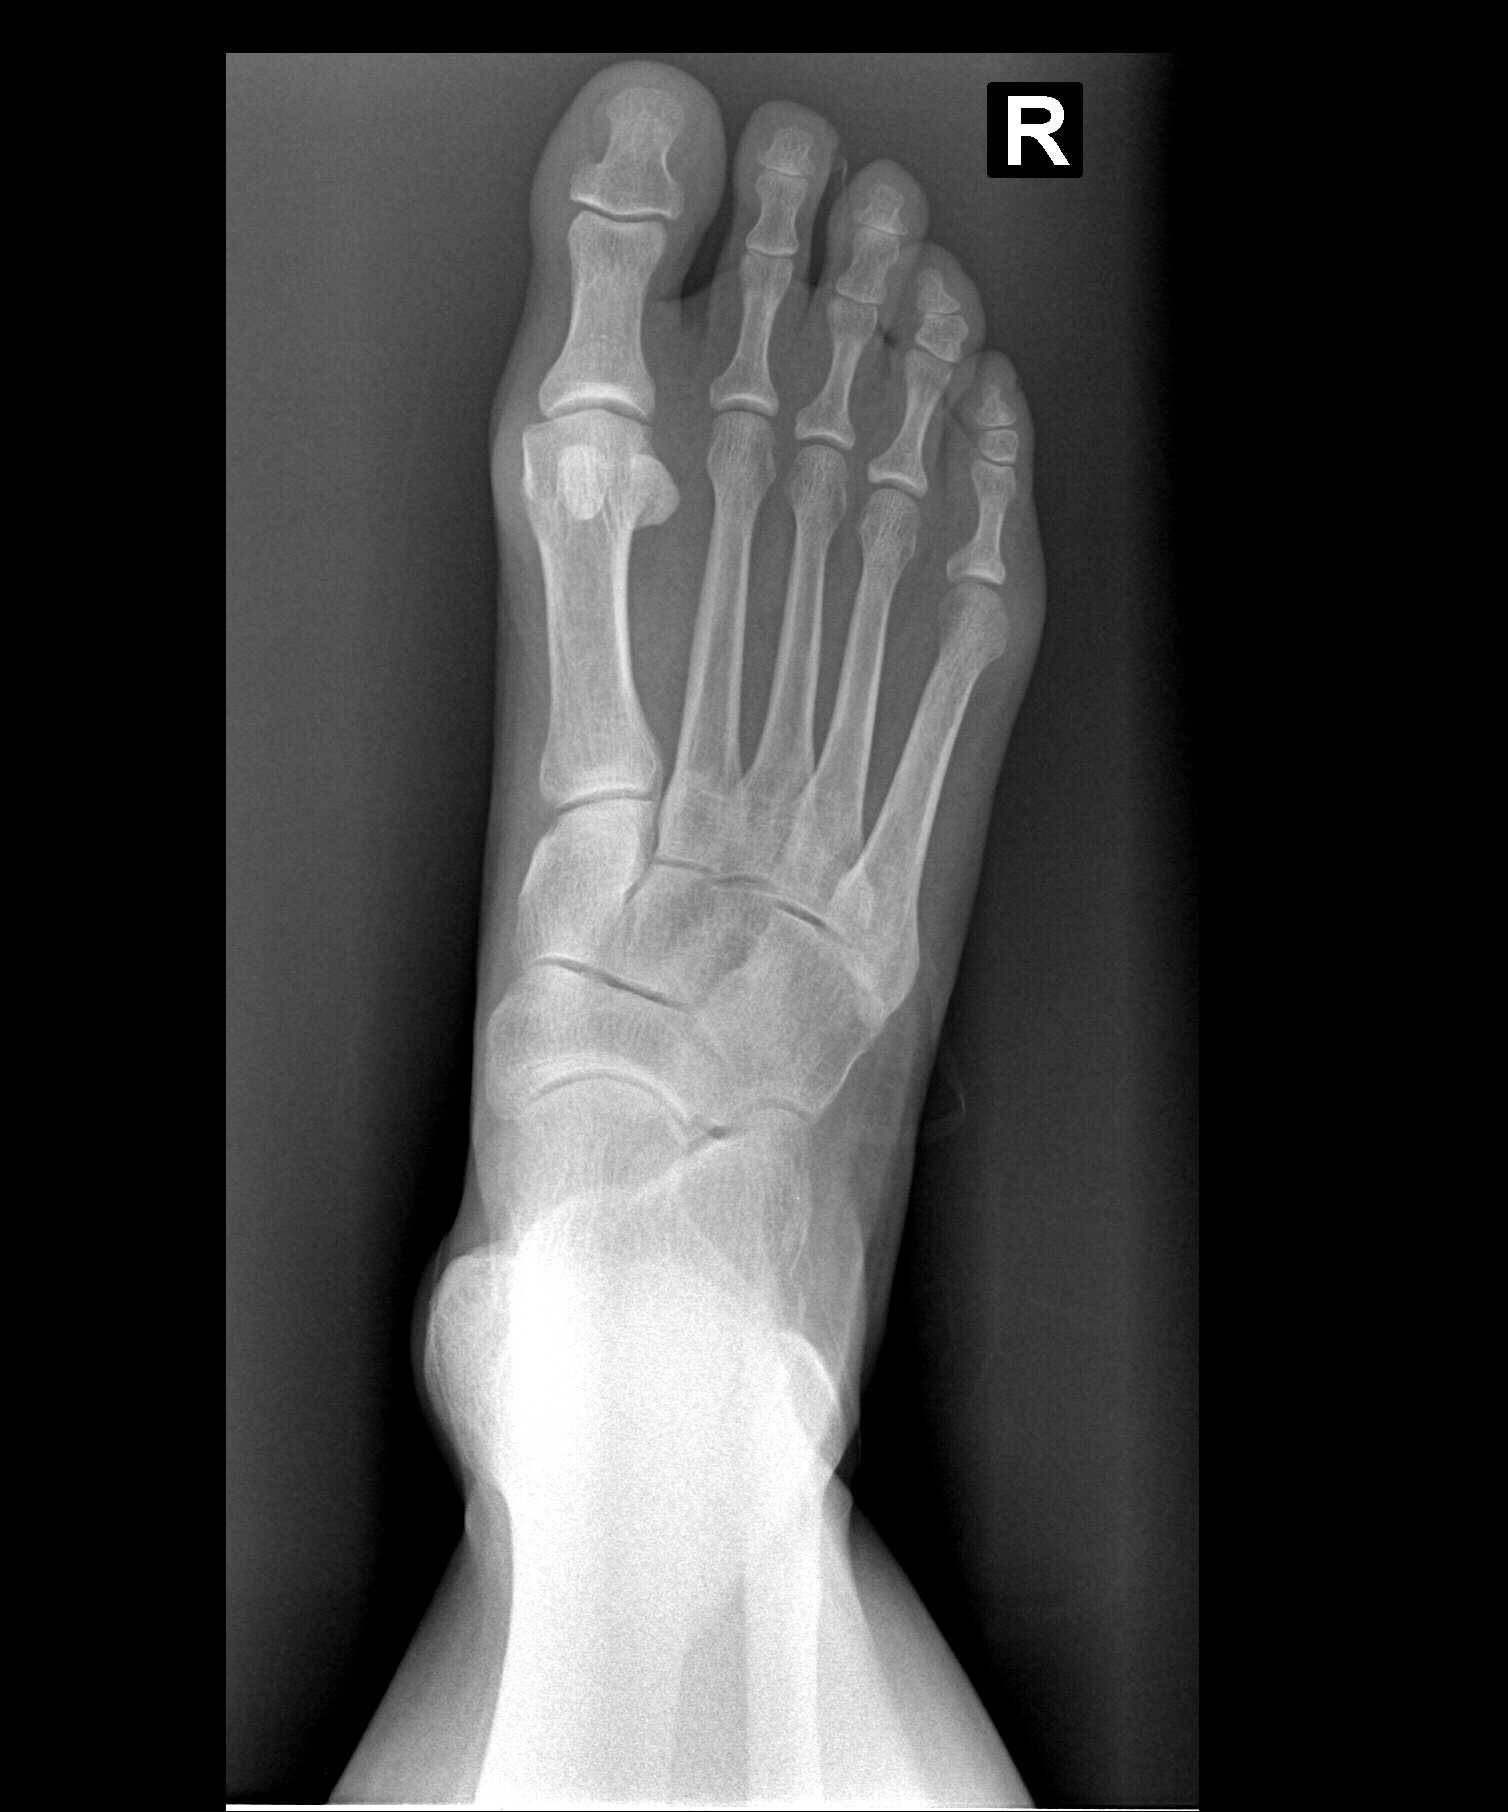

My left foot had healed sufficiently and I then had my pre-surgical appointment with Dr. Gent (see last blog). He is now going to do the same HyProCure Surgery on my right foot. My diagnosis code: 718.37- Recurrent dislocation of joint, ankle and foot; and my Surgical Procedure: 28585 definition: Open treatment of talotarsal joint dislocation, includes internal fixation, when performed.

9:00 am-This surgery went a little faster as Dr. Gent was already familiar with my anatomy and he used the Size 6 HyProCure Stent again just like my left foot. (See this link for Dr. Gent’s video demonstration of a sample stent into his foot skeleton.) I had the same wonderful anesthesiologist, David Bobiak, CRNA from Olympia Anesthesia.